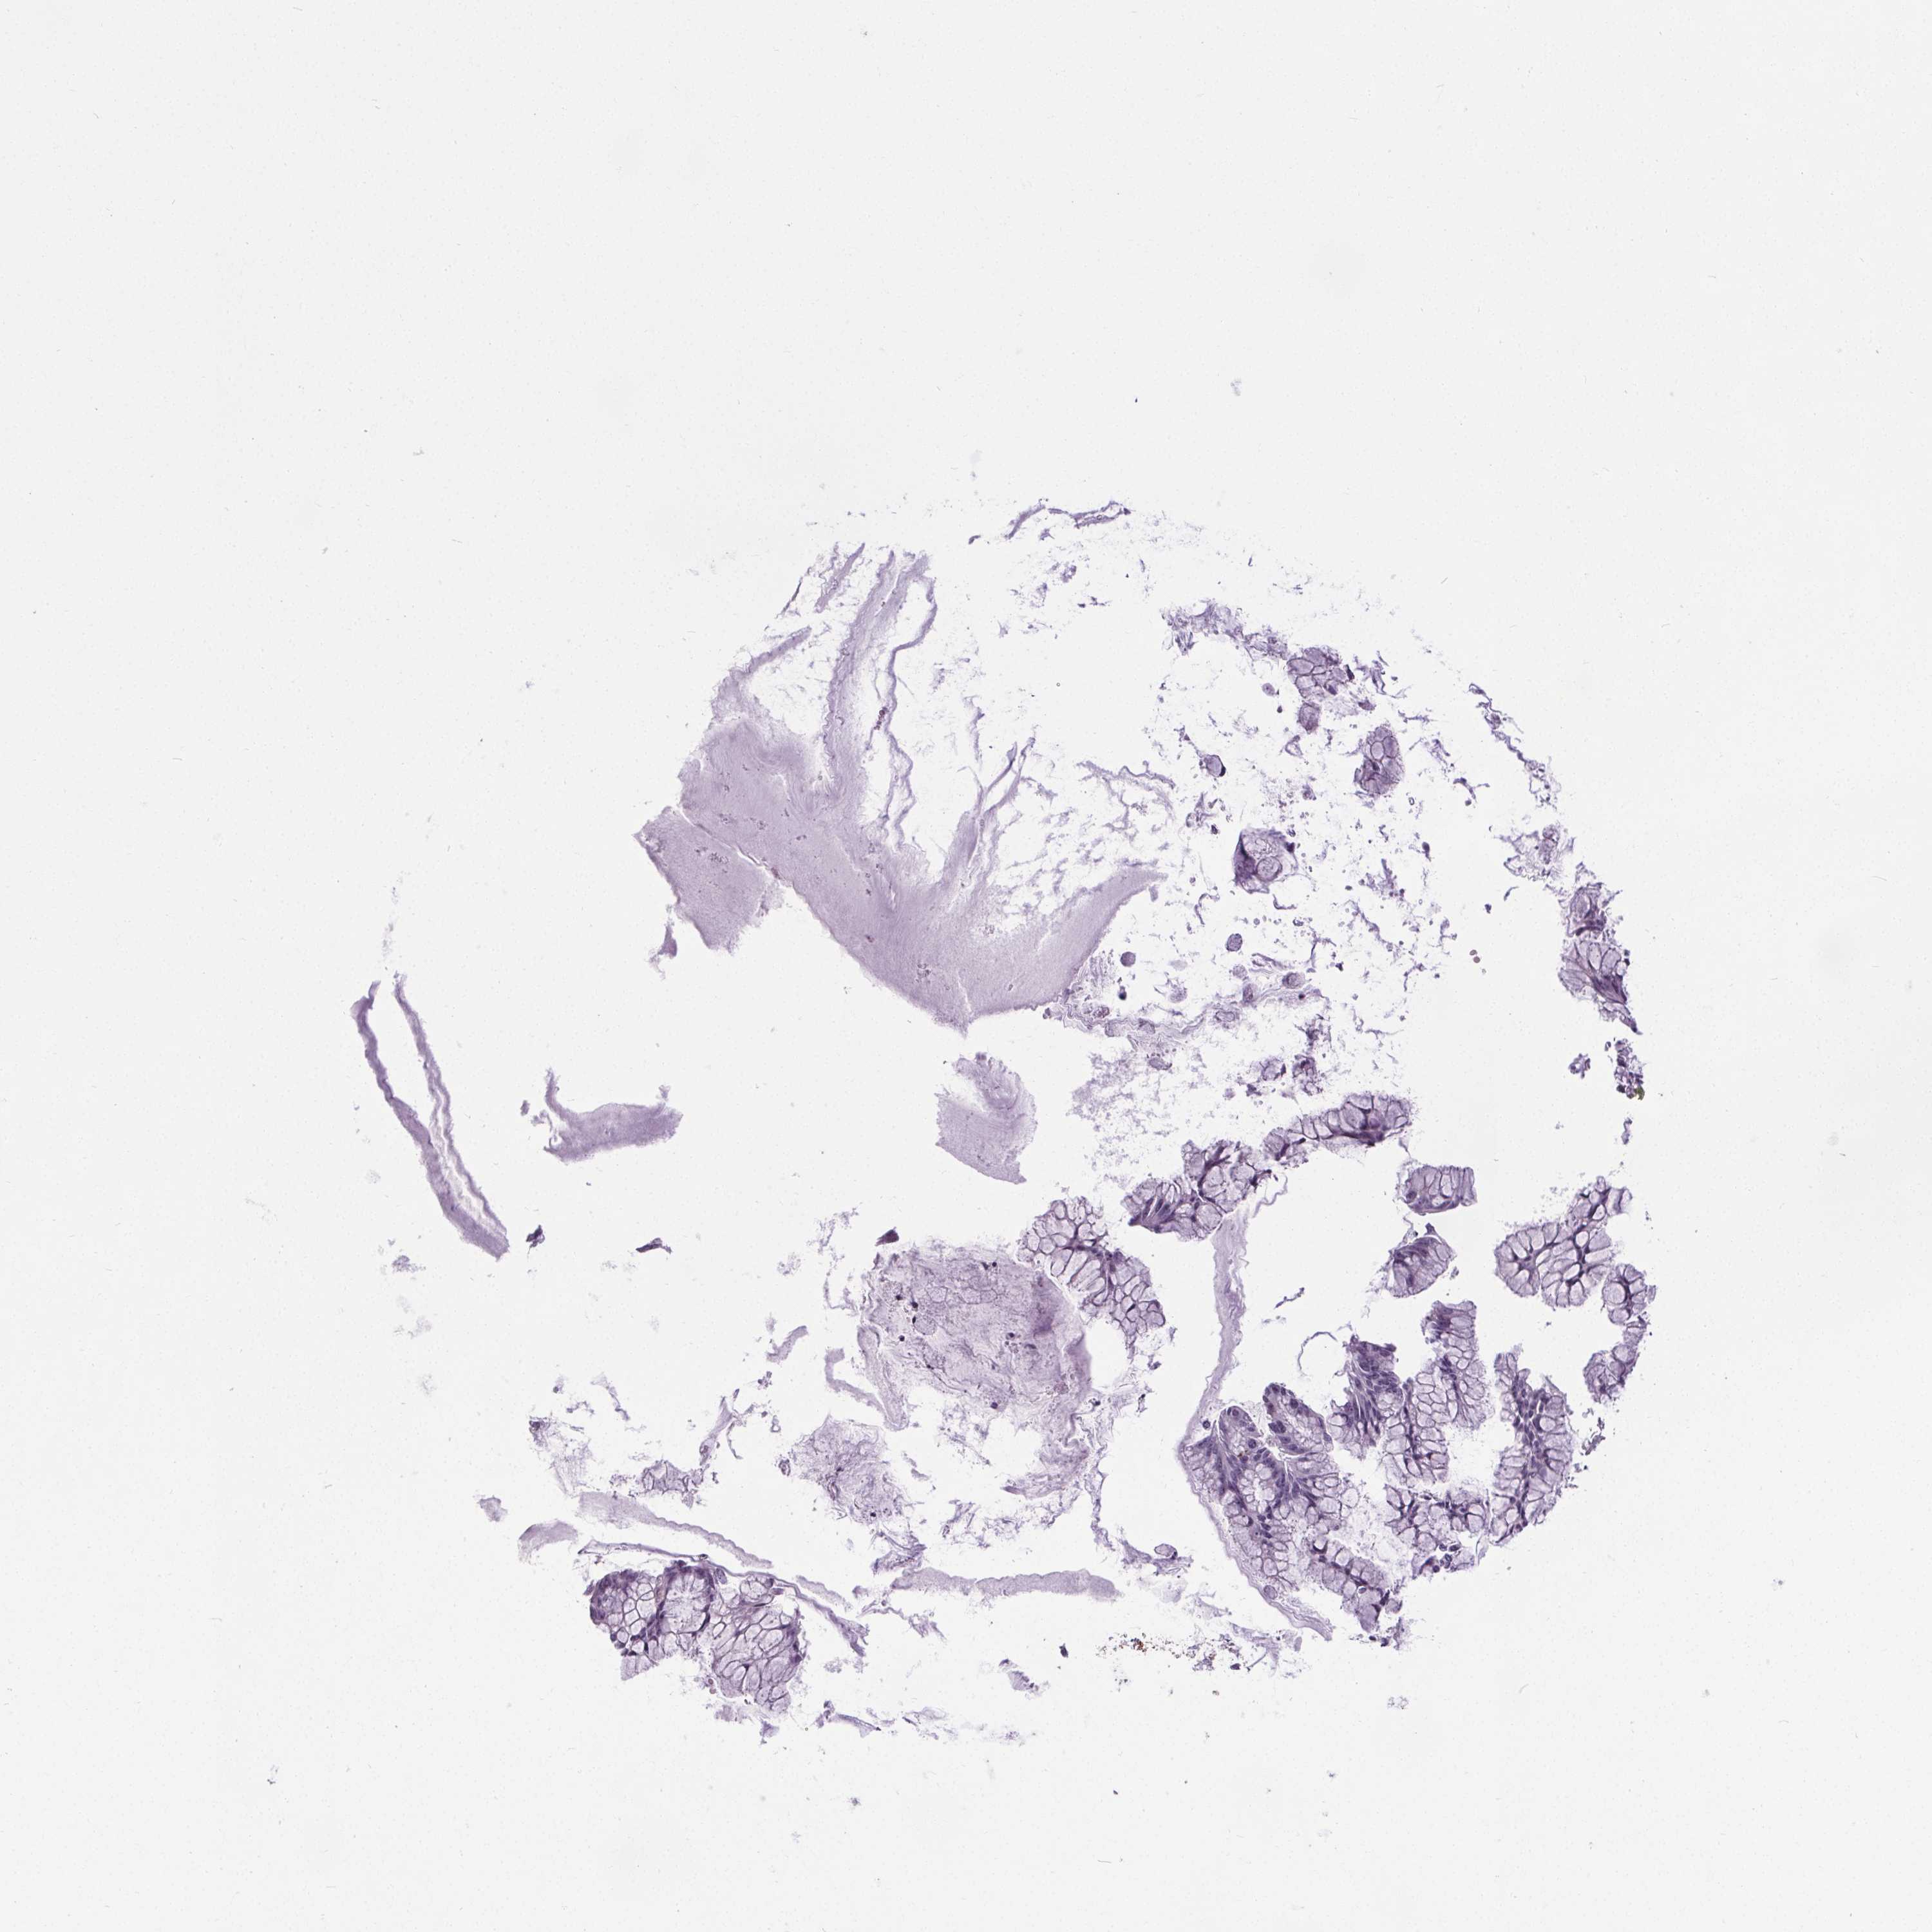

OVARIAN CANCER - Protein expressioni

A mouse-over function shows sample information and annotation data. Click on an image to view it in a full screen mode. Samples can be filtered based on level of antibody staining by selecting one or several of the following categories: high, medium, low and not detected. The assay and annotation is described here.

Note that samples used for immunohistochemistry by the Human Protein Atlas do not correspond to samples in the TCGA dataset.

Antibody stainingi

Antibody staining in the annotated cell types in the current human tissue is reported as not detected, low, medium, or high, based on conventional immunohistochemistry profiling in selected tissues. This score is based on the combination of the staining intensity and fraction of stained cells.

Each image is clickable and will lead to virtual microscopy that enables deeper exploration of all samples and also displays staining intensity scores, fraction scores and subcellular localization as well as patient and tissue information for each sample.

Antibody HPA066721

Cystadenocarcinoma, serous, NOS

Cystadenocarcinoma, mucinous, NOS

Carcinoma, endometroid